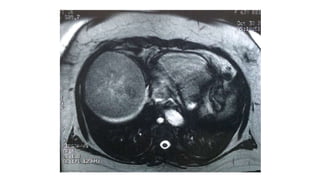

Hepatocarcinoma

• Responsable de alrededor de 1 millón de fallecimientos

• 6ª neoplasia maligna más común

• 3ª causa de mortalidad por neoplasia maligna

• 4ª y 3ª causa de mortalidad en hombres y mujeres

• 80% en cirróticos

Journal of Hepatology 2012 vol. 56 | 908–943